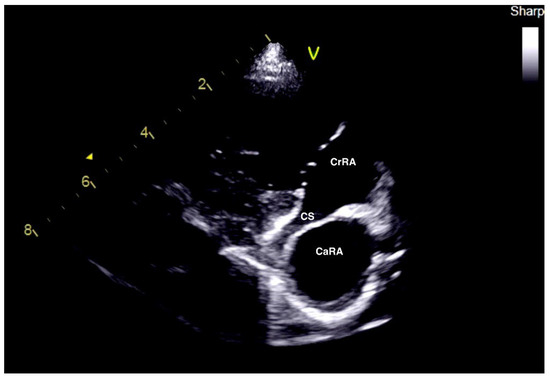

2.1. Case 1